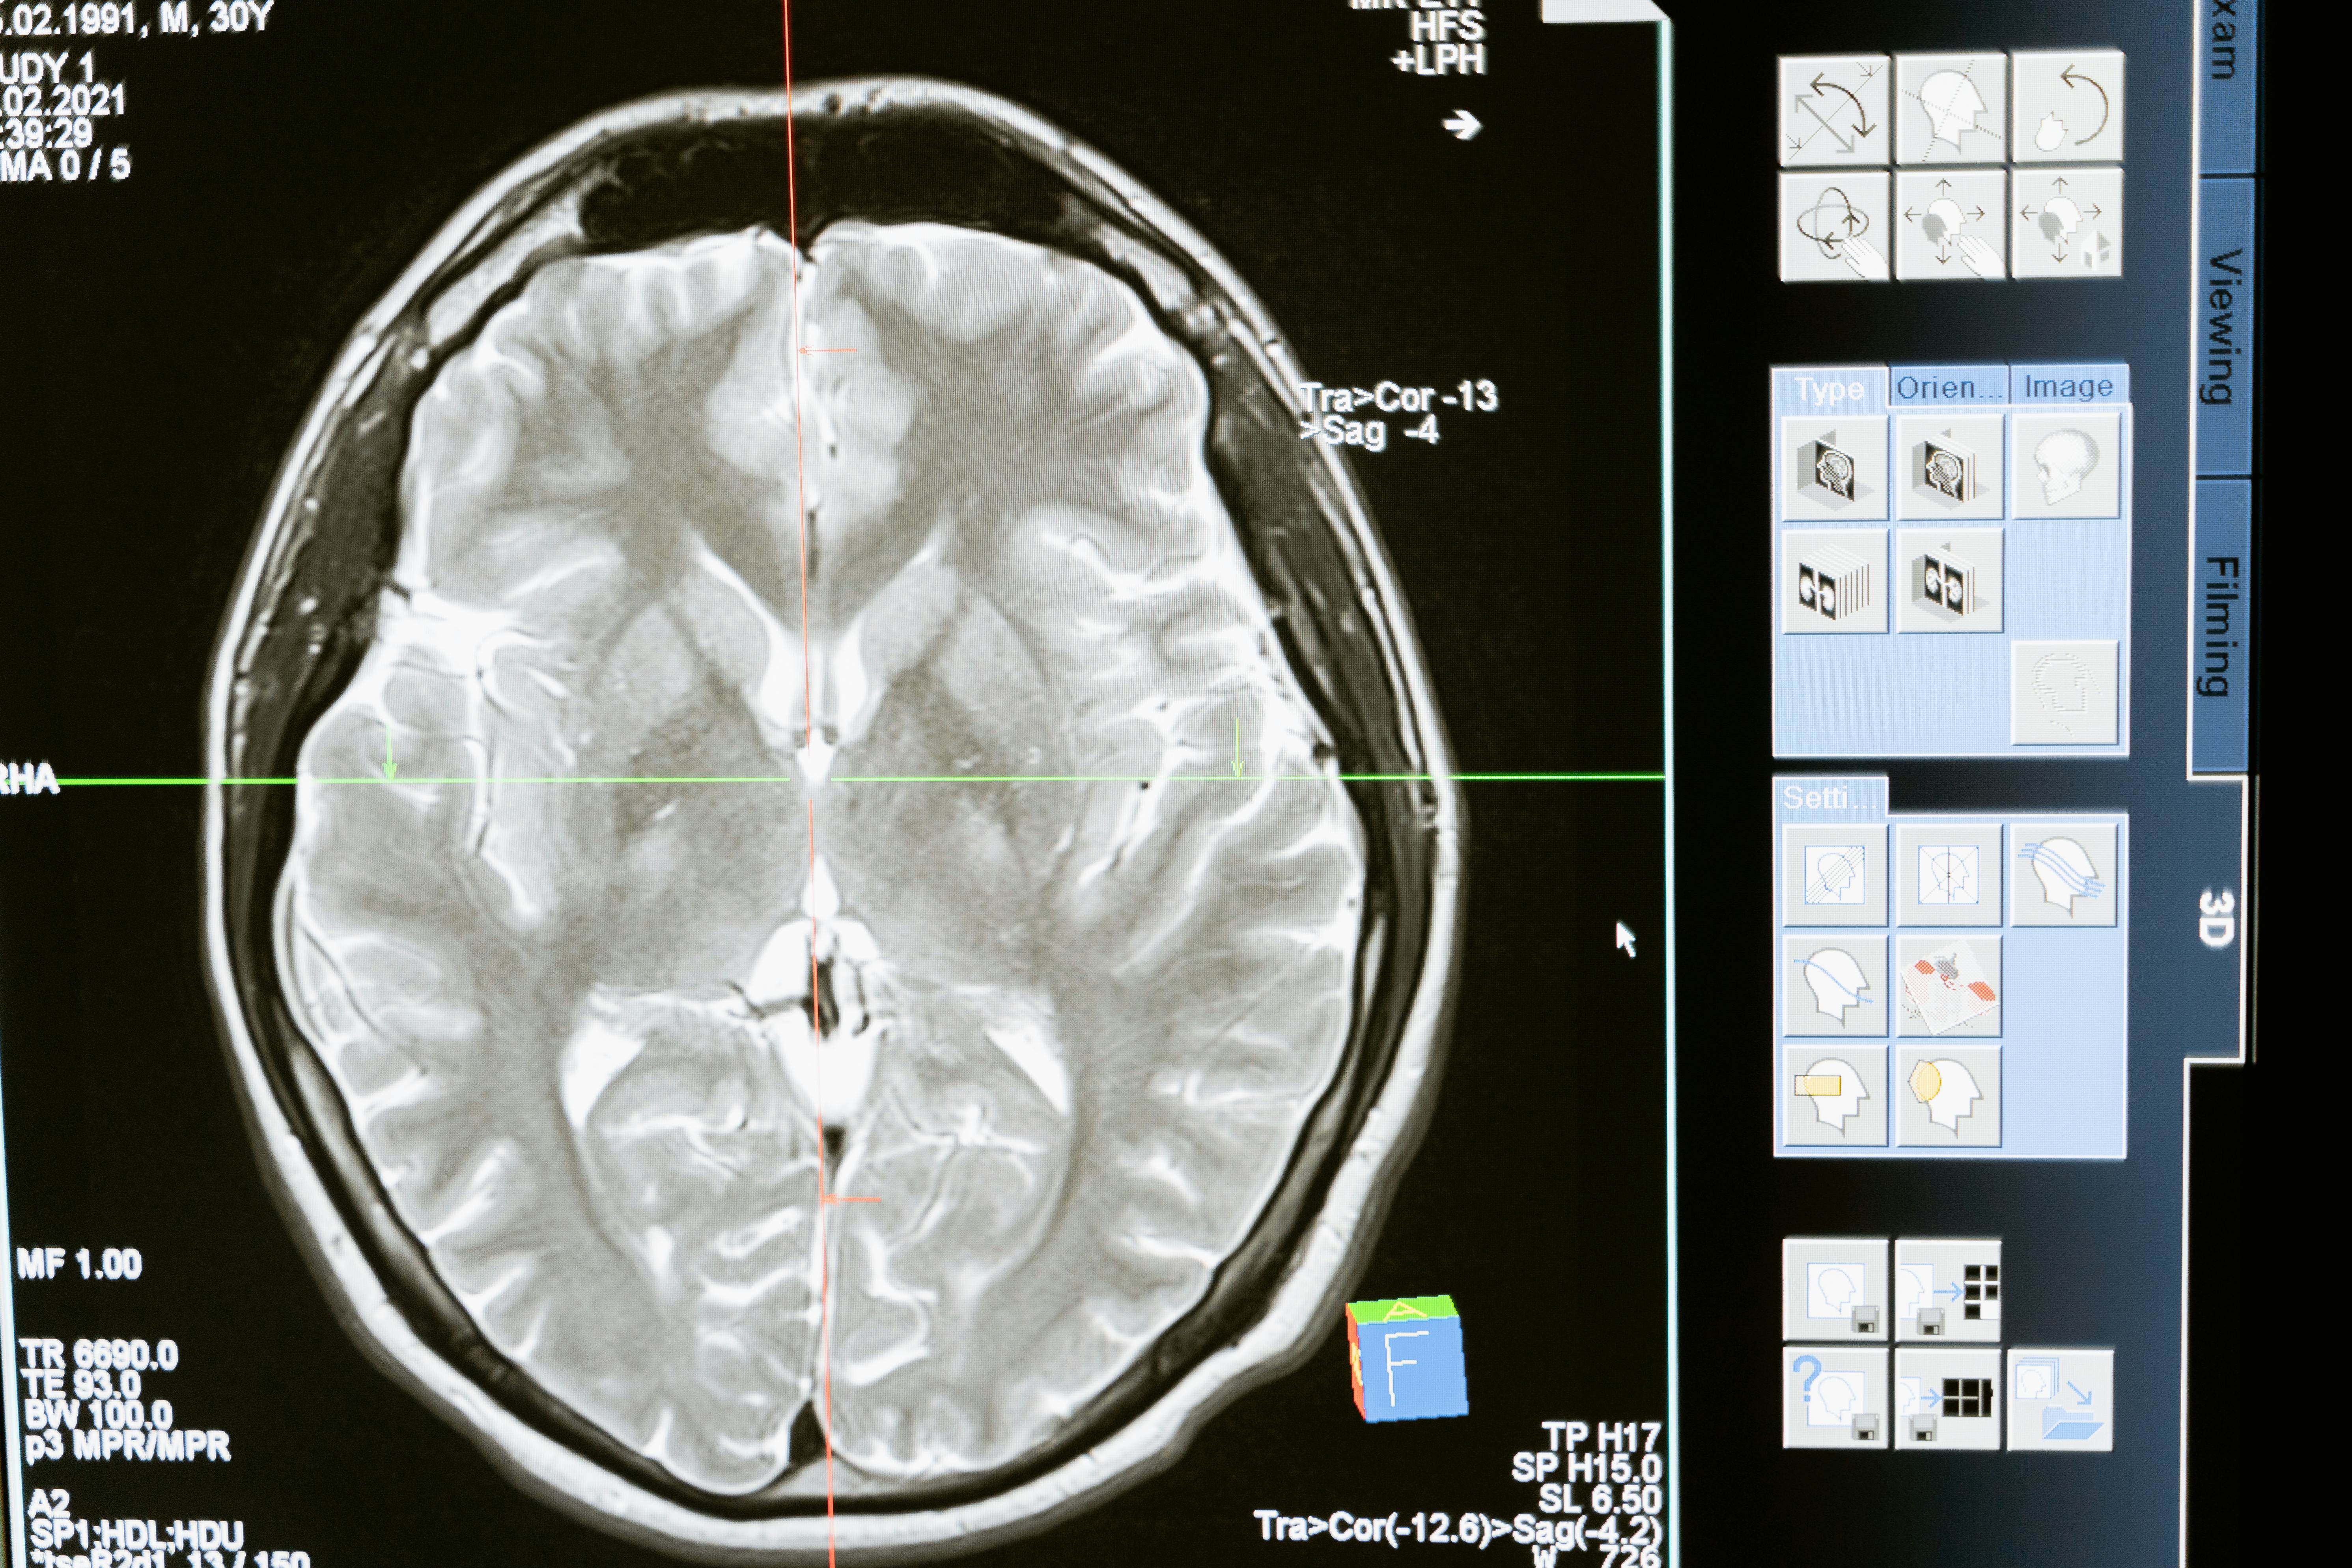

簡單來說,LDCT是一種輻射劑量更低的胸部X光電腦斷層掃描。它的輻射量大約只有傳統CT的五分之一,卻能以高解析度影像捕捉到僅0.3公分的微小結節。也就是說,傳統胸部X光可能要等腫瘤長到2公分才看得出來,而LDCT能在「癌症還在竄芽」時就把它揪出來。

醫師指出,這項技術特別擅長辨識所謂的「毛玻璃樣陰影」,這正是早期肺腺癌常見的影像特徵。更棒的是,LDCT 還能順便偵測到其他肺部異常,如肺纖維化、鈣化斑塊或慢性阻塞性肺病(COPD),一次檢查多重保障。